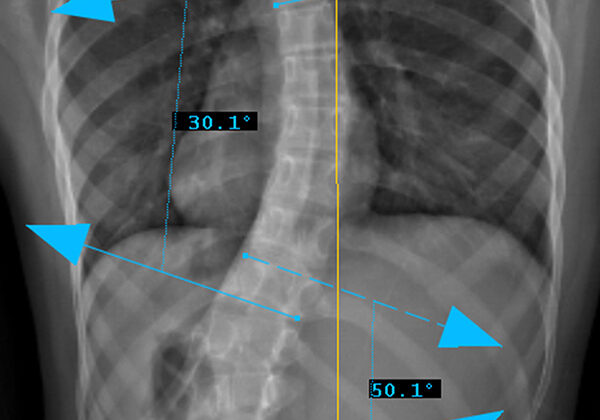

الدراسة وجدت أن سرعة نمو العمود الفقري نفسه ترتبط بتفاقم الانحناء أكثر من زيادة الطول الكلي للجسم.

أظهرت النتائج أن:

الفتيات اللواتي كان لديهن نمو أسرع في العمود الفقري كن أكثر عرضة لزيادة الانحناء بسرعة.

سرعة نمو العمود الفقري كانت مؤشرًا أقوى لتوقع تفاقم الجنف مقارنة بزيادة الطول العام.

بمعنى آخر:

إذا كان العمود الفقري ينمو بسرعة، فهناك احتمال أكبر أن يزداد الانحناء خلال تلك الفترة، حتى لو لم يكن هناك ارتفاع ملحوظ جدًا في الطول الكلي.